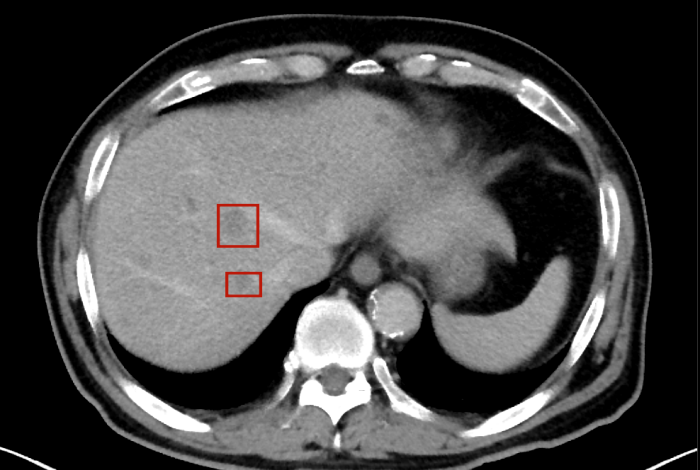

術(shù)后,萬(wàn)秀萍為黃先生做進(jìn)一步的檢查,腹部磁共振(MRI)檢查顯示:肝臟區(qū)域出現(xiàn)了轉(zhuǎn)移病灶的陰影。

轉(zhuǎn)移病灶的陰影